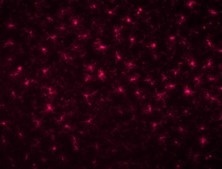

◆性能数据

与本公司常规产品(兔源多克隆抗体)的比较

|

多克隆抗体 |

单克隆抗体 |

物种:大鼠 部位:大脑皮层 样品:冰冻切片 稀释率:1:200

<数据提供> 创价大学 糖链生命系统融合研究 所 中嶋老师 |